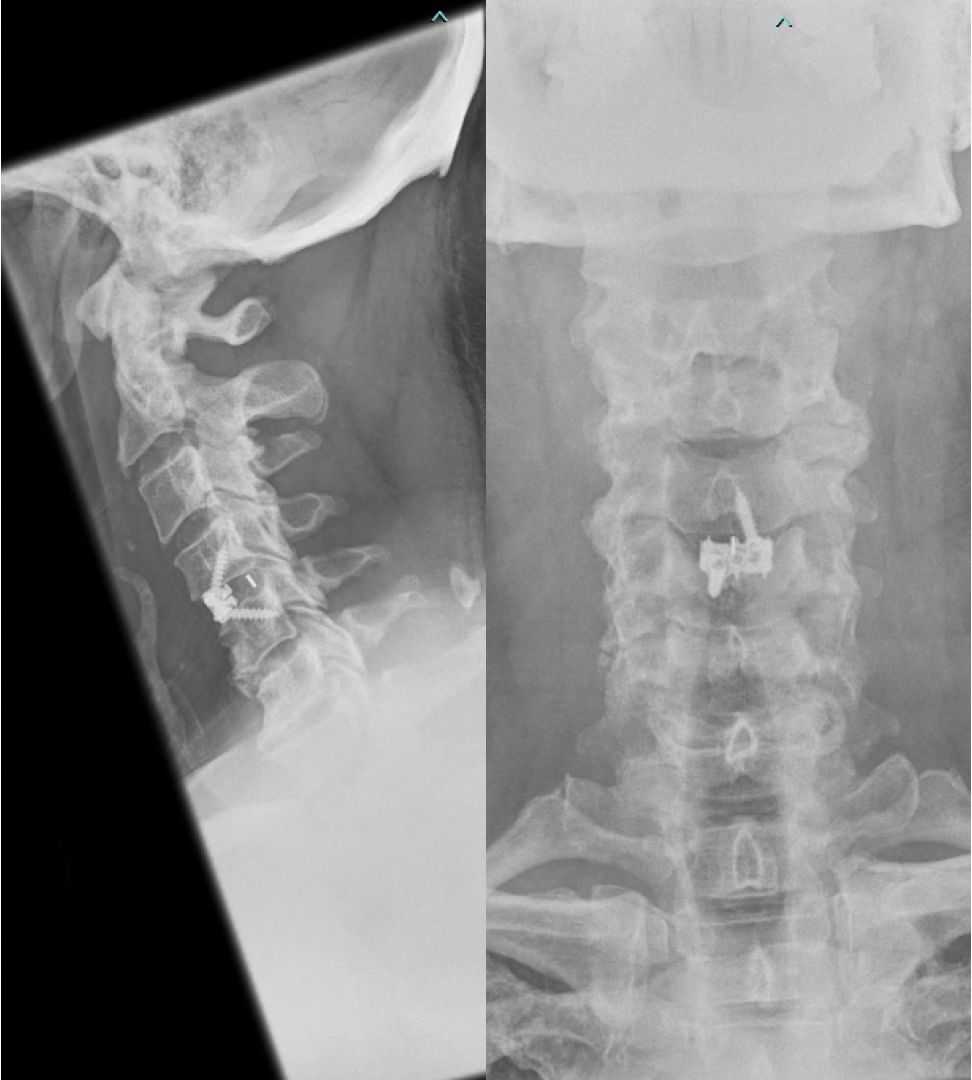

Treatment

The treatment for cervical radiculopathy and myelopathy depends on the underlying cause of the condition, the severity of symptoms and patient factors. In some cases, conservative treatments may be effective, such as rest, physical therapy, and pain medication. If conservative treatments are not effective, more invasive treatments, such as spinal injections or surgery may be required. Cervical radiculopathy can improve with time. However, cervical myelopathy tends to progress and is regarded as a surgical condition (i.e. one that will require surgery). Surgery is usually indicated for severe or worsening symptoms, such as severe uncontrollable pain, weakness or numbness in the arms or legs, difficulty walking, or loss of bladder or bowel control. Surgery for cervical radiculopathy is generally indicated to improve arm pain whereas surgery for cervical myelopathy is to prevent further deterioration.